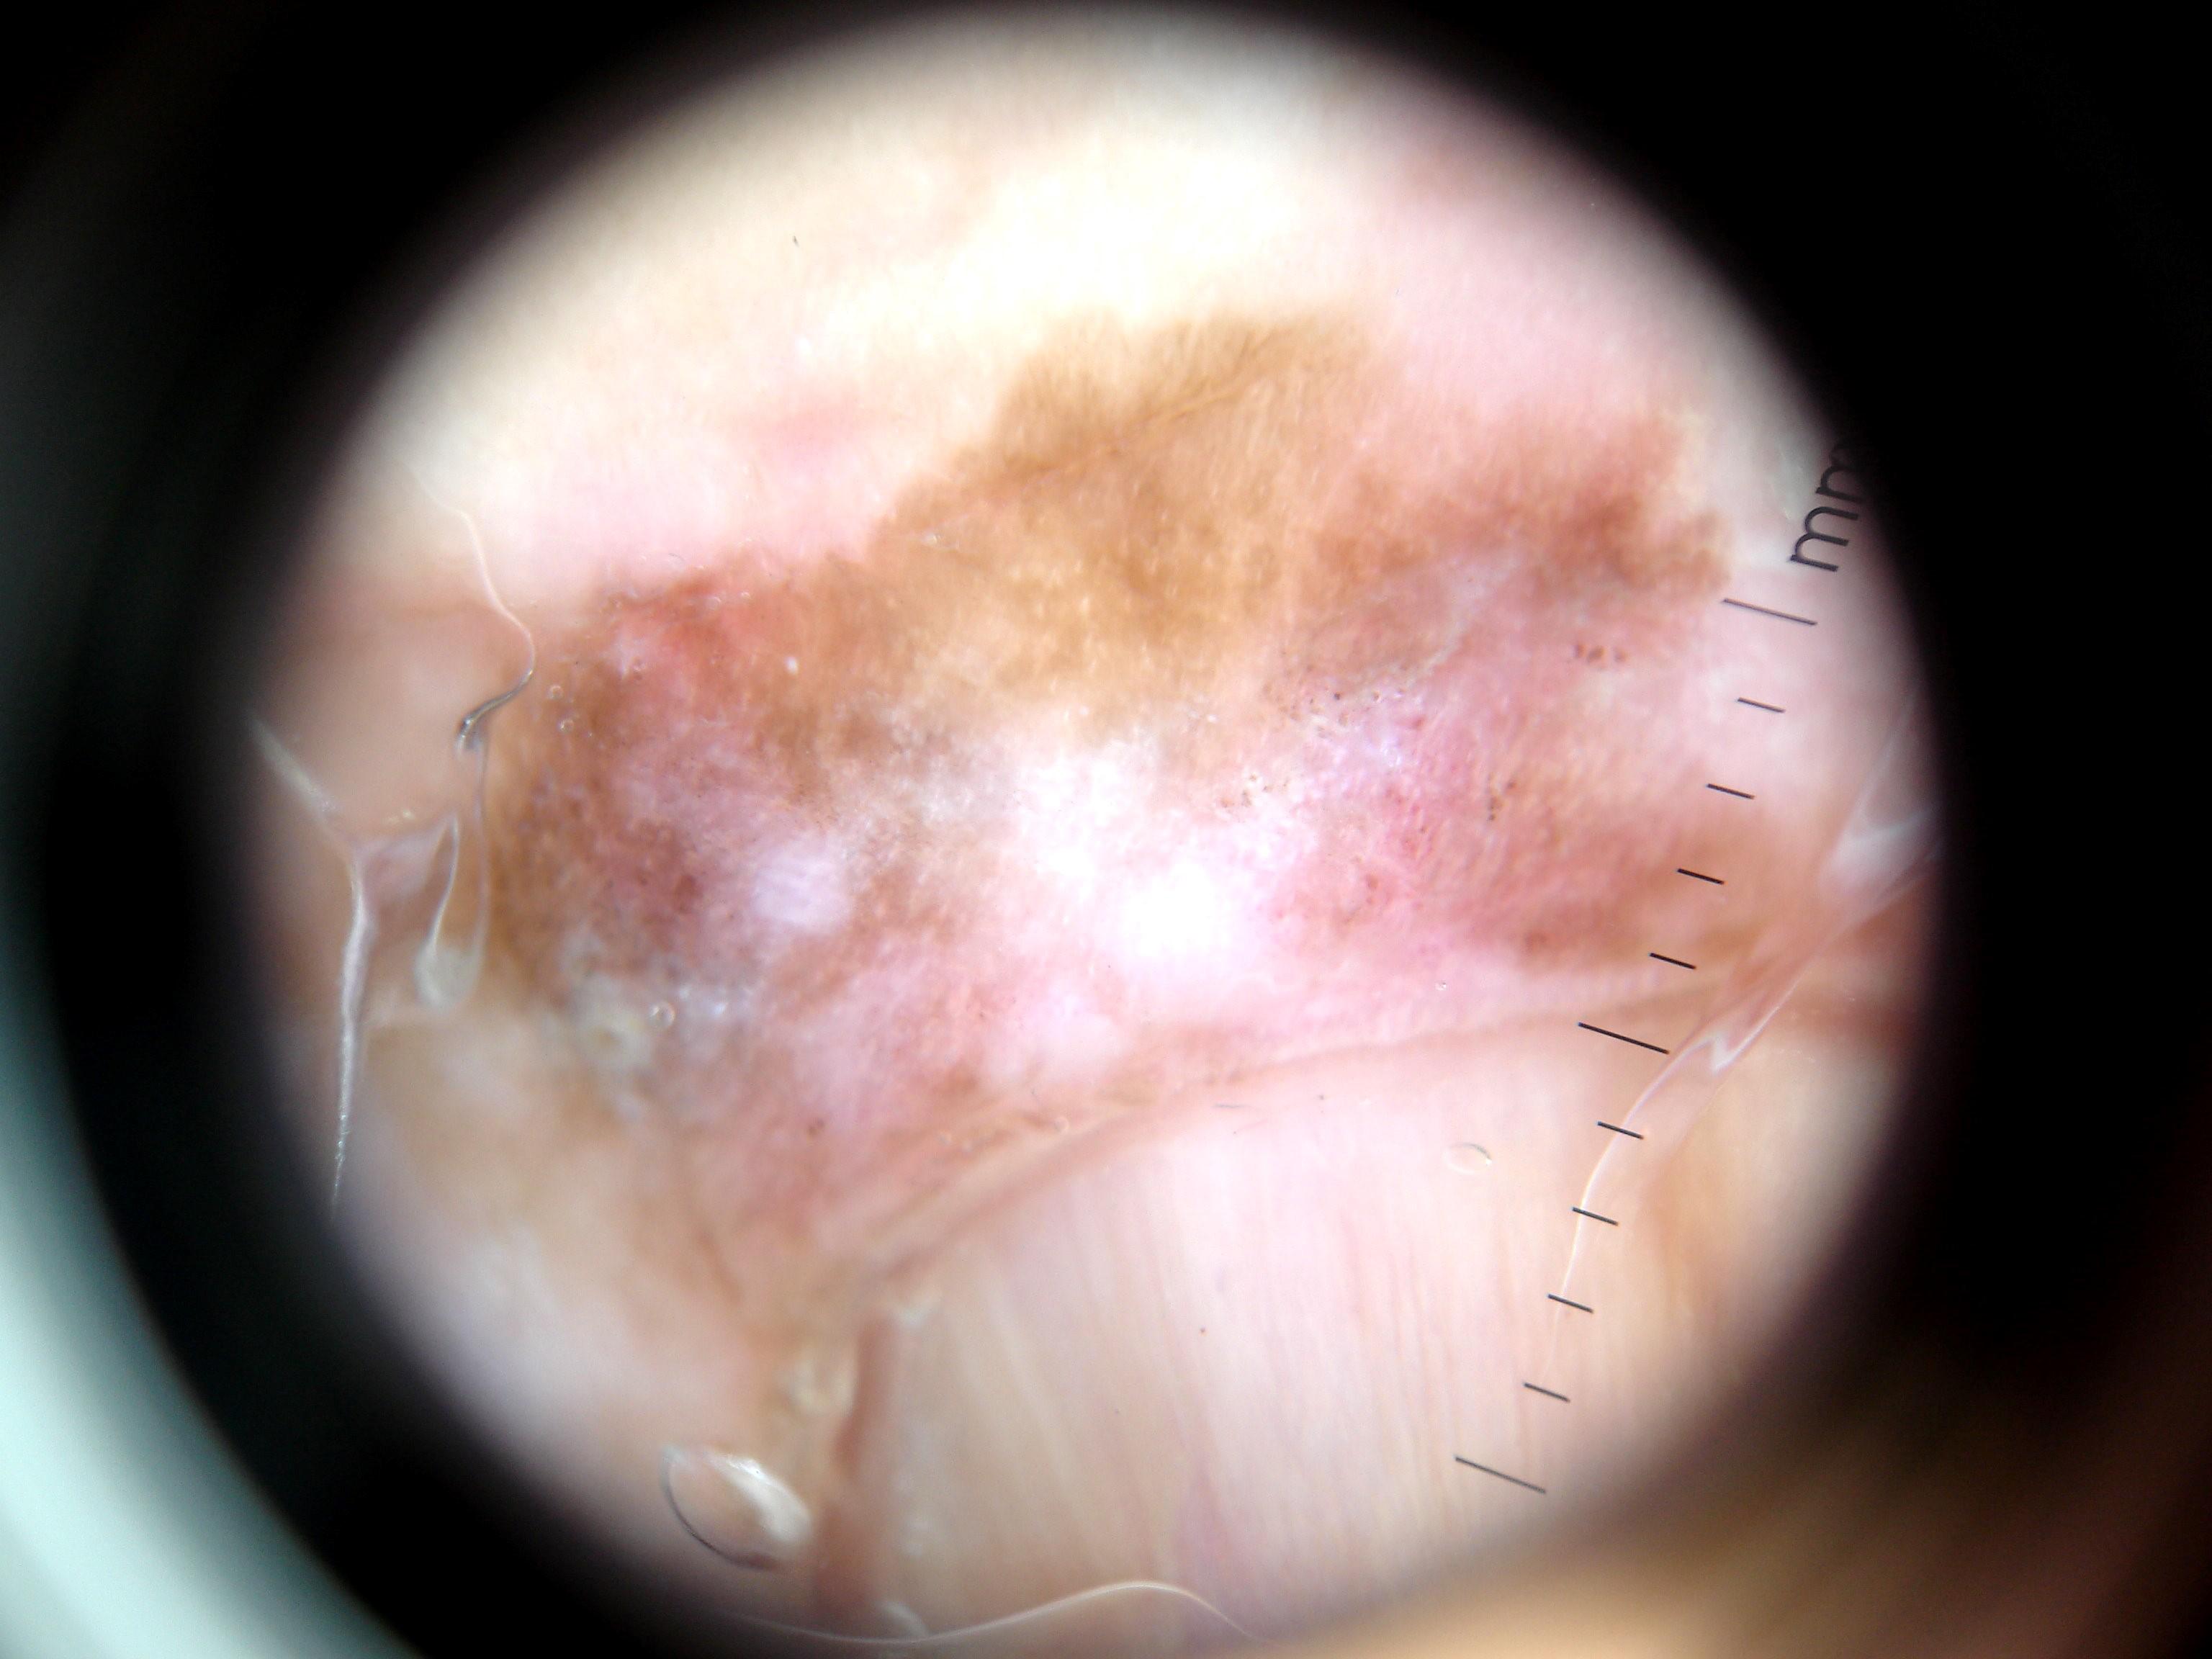

{

"age_approx": 65,

"anatom_site_general": "upper extremity",

"anatom_site_special": "acral NOS",

"concomitant_biopsy": true,

"dermoscopic_type": "contact non-polarized",

"diagnosis_1": "Malignant",

"diagnosis_2": "Malignant melanocytic proliferations (Melanoma)",

"diagnosis_3": "Melanoma in situ",

"diagnosis_confirm_type": "histopathology",

"family_hx_mm": false,

"image_type": "dermoscopic",

"mel_thick_mm": "0.00",

"melanocytic": true,

"patient_id": "IP_3069248",

"personal_hx_mm": false,

"sex": "male"